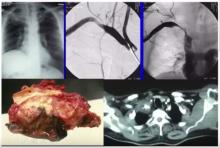

Superior Sulcus Tumor Resection [1]

Philippe Dartevelle of Marie Lannelongue Hospital and Paris-Sud University, Paris, France, discusses an anterior approach to superior sulcus tumors.